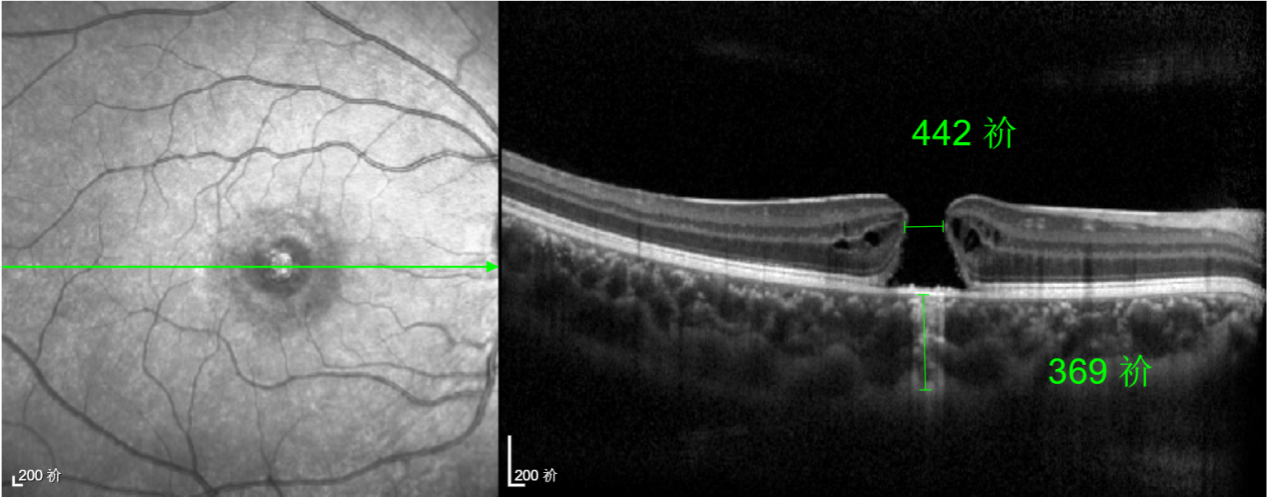

半年前的一次意外,誠(chéng)誠(chéng)(化名)右眼不慎受傷導(dǎo)致黃斑裂孔。從此,他的“視”界不再清晰,也不再有直線條……

經(jīng)過(guò)詳細(xì)的檢查和評(píng)估,王曉波主任決定采用“內(nèi)界膜翻轉(zhuǎn)覆蓋聯(lián)合粘彈劑固定術(shù)”為誠(chéng)誠(chéng)進(jìn)行治療。

術(shù)中,醫(yī)生精細(xì)剝離黃斑區(qū)的內(nèi)界膜后,并非直接丟棄,而是巧妙地給它翻個(gè)面,讓它變成一塊天然“創(chuàng)可貼”,嚴(yán)密覆蓋在黃斑裂孔的表面。覆蓋的內(nèi)界膜像微型支架一樣撐住裂孔邊緣,防止它擴(kuò)大;同時(shí),這層膜本身含有能促進(jìn)生長(zhǎng)的“養(yǎng)分”,能顯著刺激裂孔周圍的視網(wǎng)膜組織像爬山虎一樣快速生長(zhǎng)、蔓延過(guò)來(lái),最終把裂孔“補(bǔ)”好。

除此之外,利用自體組織覆蓋為黃斑裂孔提供了理想的愈合環(huán)境,裂孔閉合速度顯著快于傳統(tǒng)方法。誠(chéng)誠(chéng)接受手術(shù)24小時(shí)后,檢查可見(jiàn)內(nèi)界膜瓣位置良好;術(shù)后1個(gè)月,黃斑裂孔已經(jīng)閉合,視力恢復(fù)到0.5;術(shù)后兩個(gè)月,視力進(jìn)一步提升到0.7。